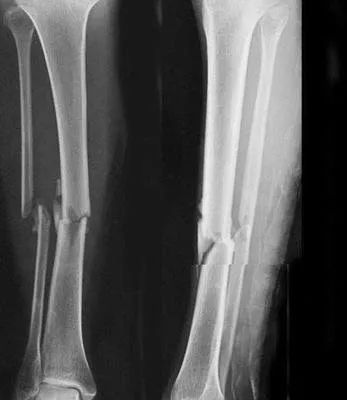

曾经骨折过能参军吗?

骨、关节、滑囊疾病或损伤及其后遗症,骨、关节畸形,胸廓畸形,习惯性脱臼,颈、胸、腰椎骨折史,腰椎间盘突出,强直性脊柱炎,影响肢体功能的腱鞘疾病,不合格。

以下情况合格:

1)可自行矫正的脊柱侧弯;

2)四肢单纯性骨折,治愈1年后,X线片显示骨折线消失,复位良好,无功能障碍及后遗症(条件兵除外);

3)关节弹响排除骨关节疾病或损伤,影响正常功能的;

4)大骨节病仅指、趾关节稍粗大,无自觉症状,无功能障碍(仅陆勤人员);

5)轻度胸廓畸形(条件兵除外)。